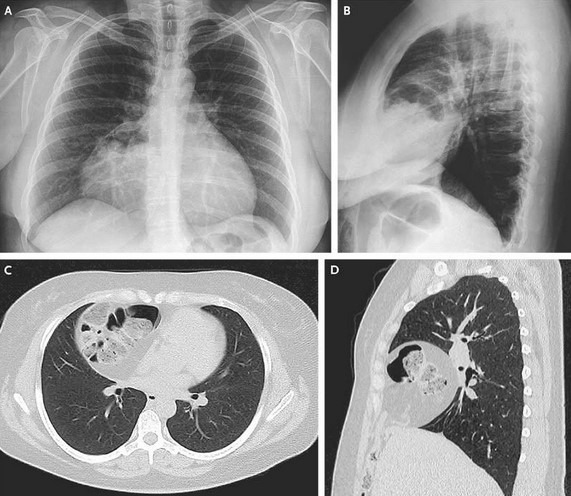

Анатомия диафрагмы и треугольника Бохдалека